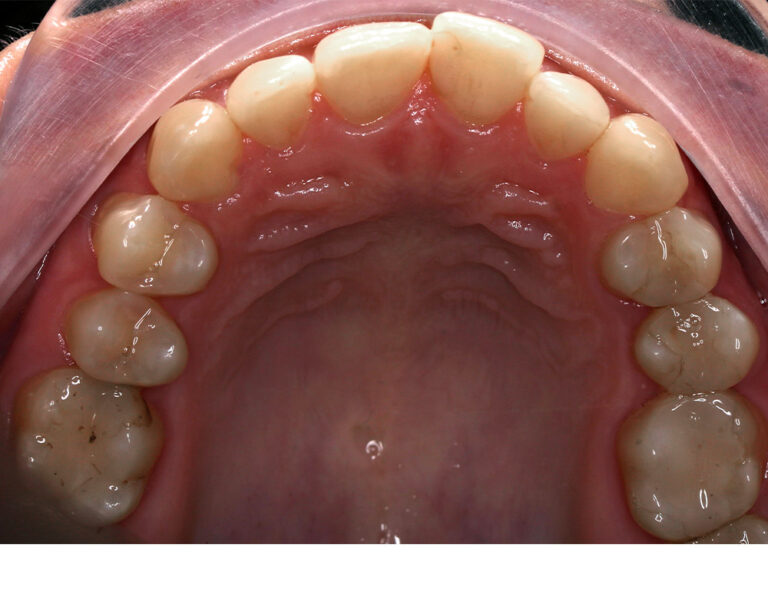

Кейс 13

Булгач (Мочалова) Галина Игоревна

Количество кап ВЧ 19

Количество кап НЧ 24

ДО

ПОСЛЕ